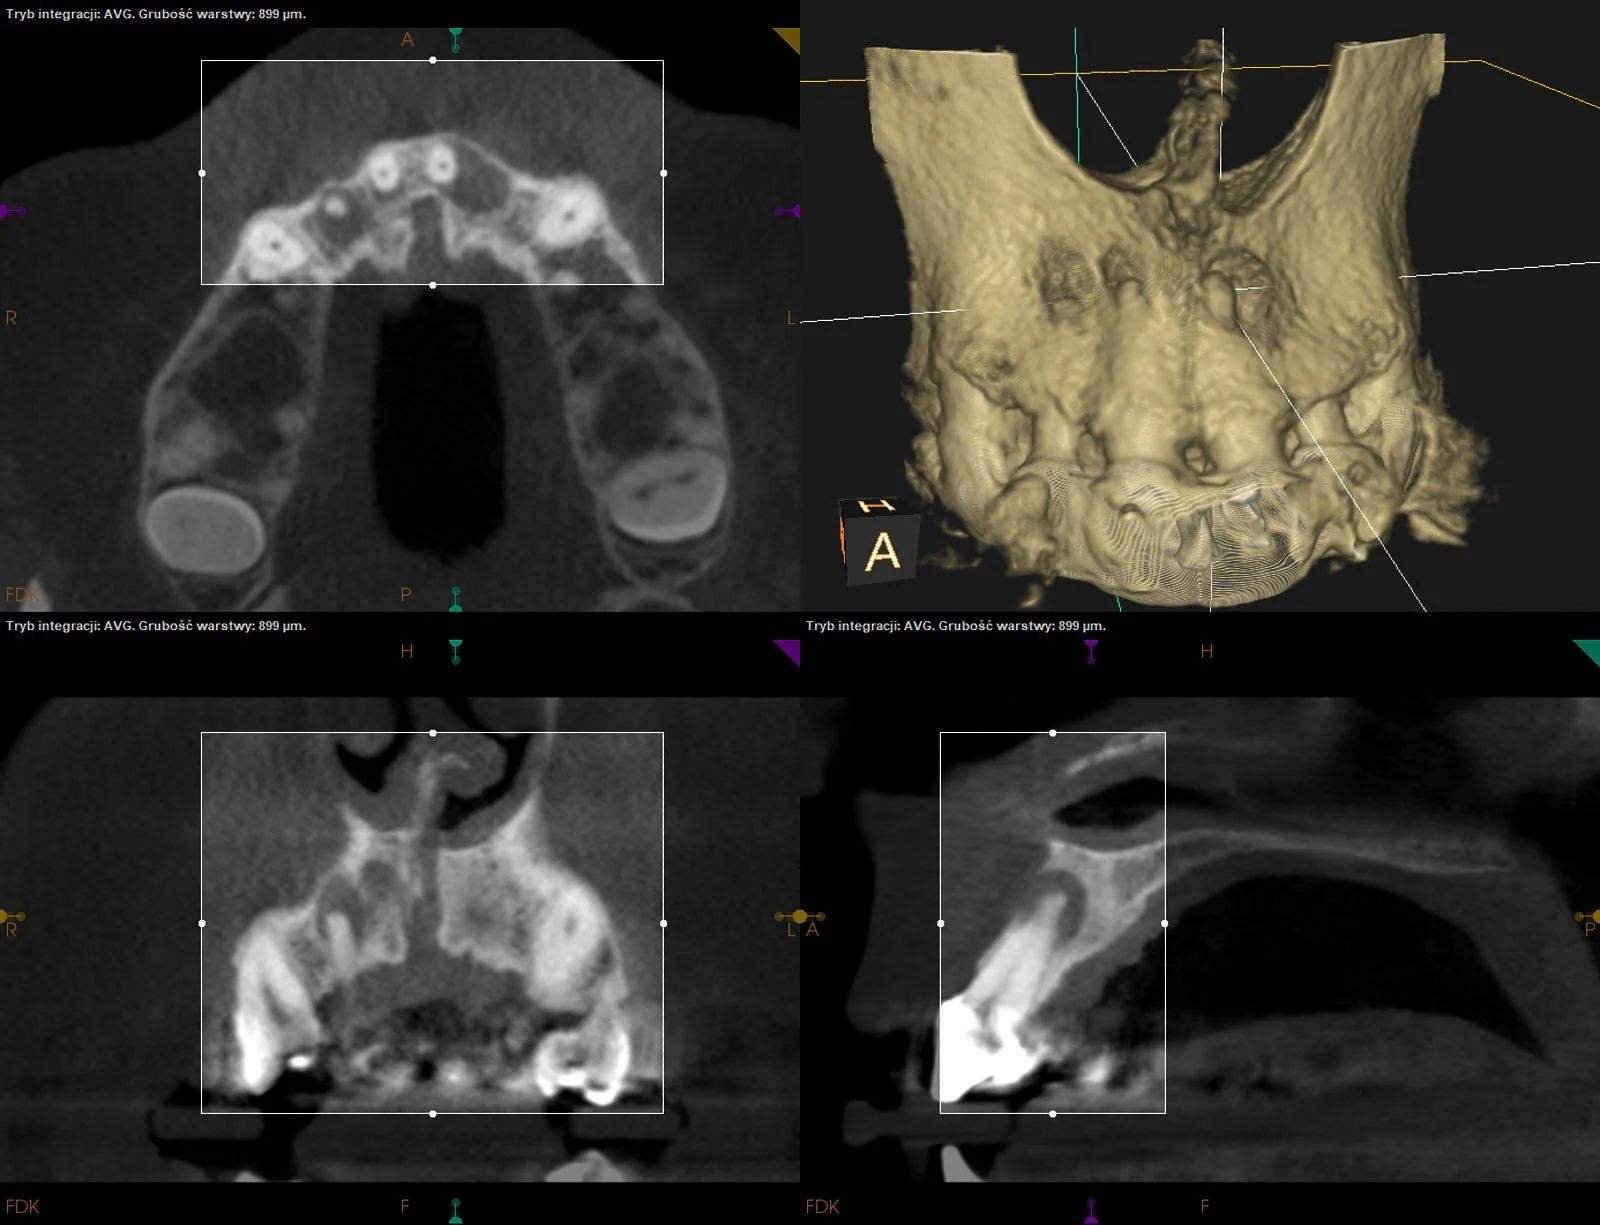

Rozległe zmiany okołowierzchołkowe przy wszystkich siekaczach szczęki po urazie w przeszłości. W następstwie leczeń kanałowych doszło do regeneracji obszaru kości przy wierzchołkach d.12,11 i 22, a d.21 został poddany resekcji wierzchołka korzenia.